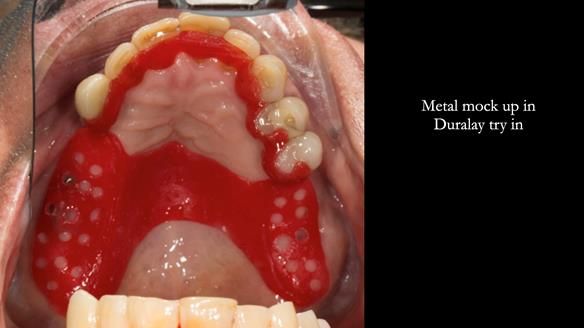

A metal-based upper RPD was made,

with metal backings incorporated to future-proof the design

should further teeth fail.